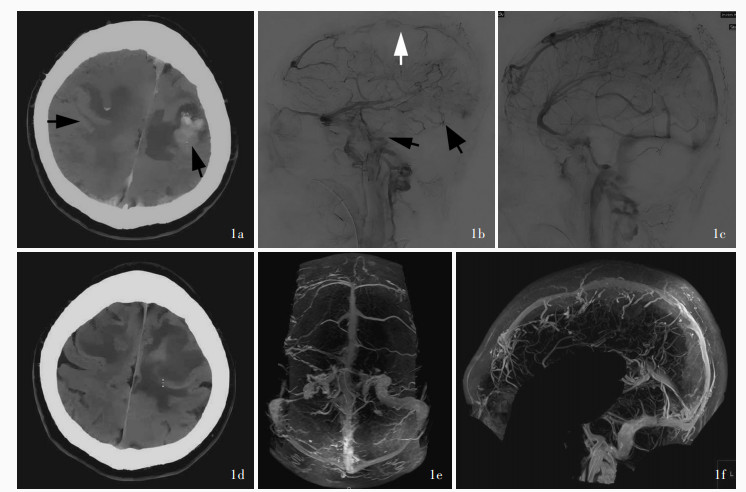

孙刘严, 郭新宾, 魏森, 杨震, 王晶晶, 管生. 支架取栓联合局部溶栓治疗重型颅内静脉窦血栓形成临床研究. 介入放射学杂志, 2021, 30: 643- 646.

Sun LY, Guo XB, Wei S, Yang Z, Wang JJ, Guan S. Stent ‐ retrievers combined with local thrombolysis for the treatment of severe cerebral venous sinus thrombosis: a clinical study. Jie Ru Fang She Xue Za Zhi, 2021, 30: 643- 646.